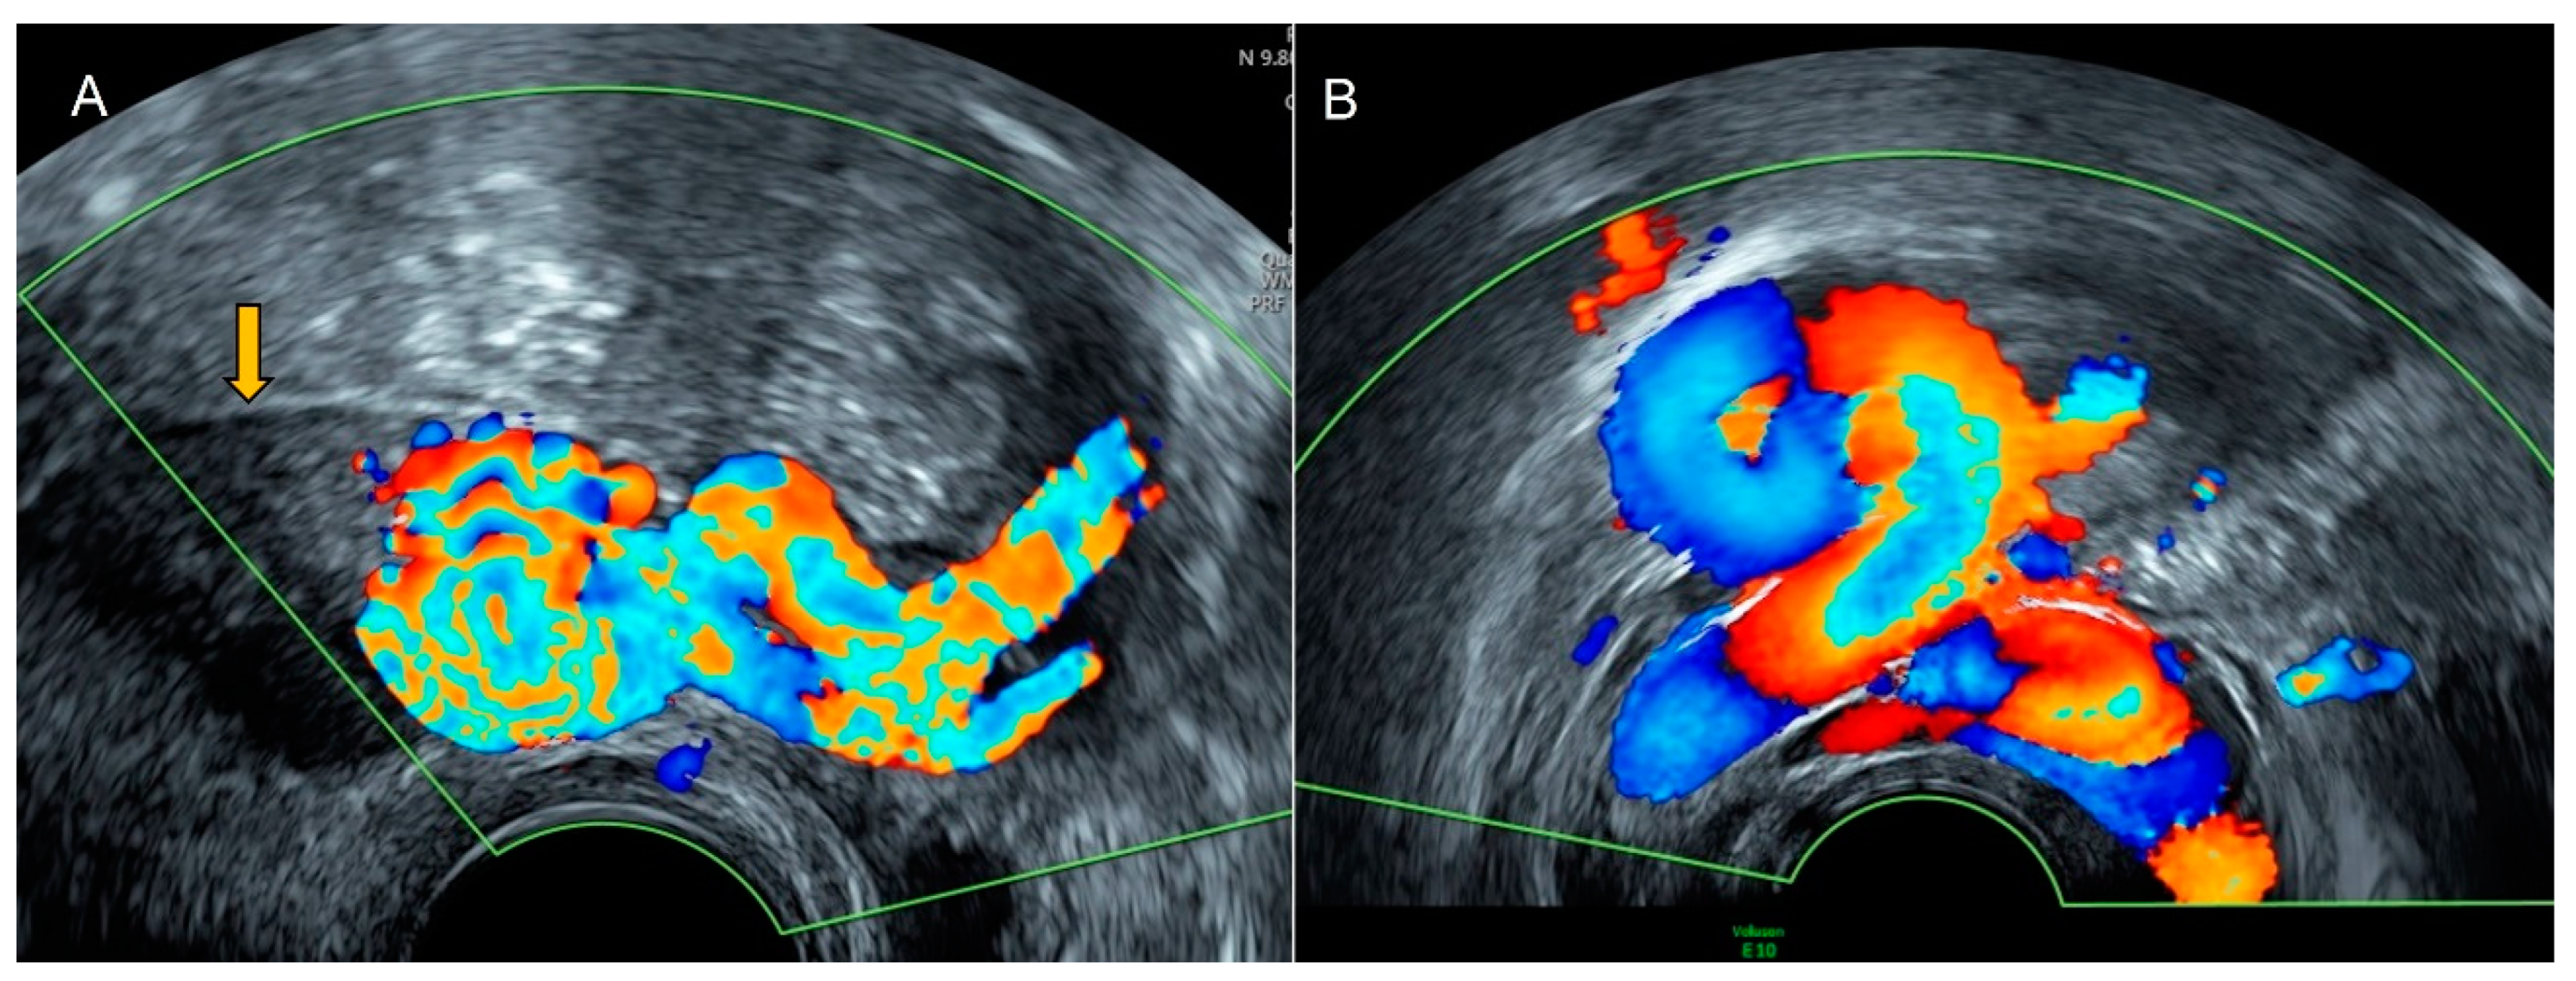

4.1. Pelvic Congestion

4.2. Thrombosis

4.3. Aneurysm

- Graupera, B.; Pascual, M.A.; Garcia, P.; Di Paola, R.; Ubeda, B.; Tresserra, F. Atypical ultrasonographic presentation of ovarian vein thrombosis. Eur. J. Gynaecol. Oncol. 2011, 32, 439–440. [Google Scholar]